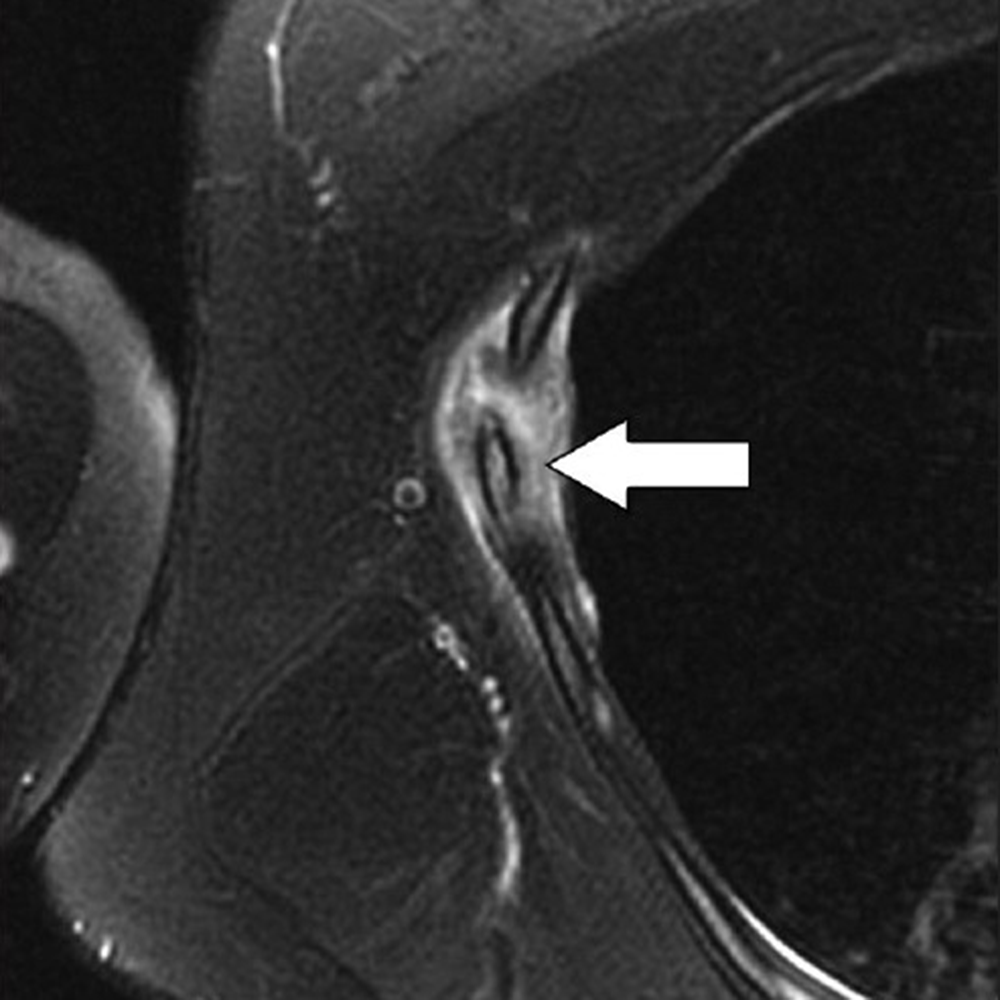

MRI provides excellent contrast to show costal cartilage fractures, which will appear as linear areas of high signal intensity against a background of low-signal-intensity costal cartilage [8]. Although MRI has superb spatial resolution and contrast, its relatively higher cost and susceptibility to respiratory motion artifacts decrease its effectiveness, when compared with CT. Ultrasound may also prove useful, given the superficial location of costochondral structures, and may show a focal stepoff at the fracture area [1]. As previously mentioned, costal cartilage injuries may occur at the sternochondral or costochondral junctions. At these locations, chondral and adjacent bone marrow edema may be present on MRI and represent the dominant findings related to traumatic injury. Treatment of costal cartilage injuries include NSAIDs, taping and immobilization belts, and rest for 2–3 weeks. In certain situations, such as treatment of professional athletes, pain can be mitigated by local injections of anesthetic [8]. An important differential diagnosis to consider when entertaining the possibility of a costochondral injury is Tietze syndrome. In this rare entity, inflammation of the sternochondral junction (the most common symptom) can occur spontaneously and lead to focal pain without any specific initiating event. The cause of Tietze syndrome is uncertain, and the condition usually affects younger patients (< 40 years old). On MRI, this entity may show edematous change surrounding the sternochondral junction, which is best seen on fat-suppressed T2-weighted images [10]. CT may not provide enough tissue contrast for adequate detection. Given that Tietze syndrome is usually self-limited, its treatment includes rest, NSAIDs, and local anesthetic injections in refractory cases.